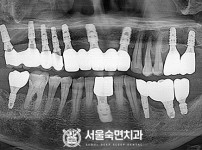

임플란트-전후사진1

치과를-선택할-때-꼭-확인하세요-서울숙면치과-임플란트-전후사진